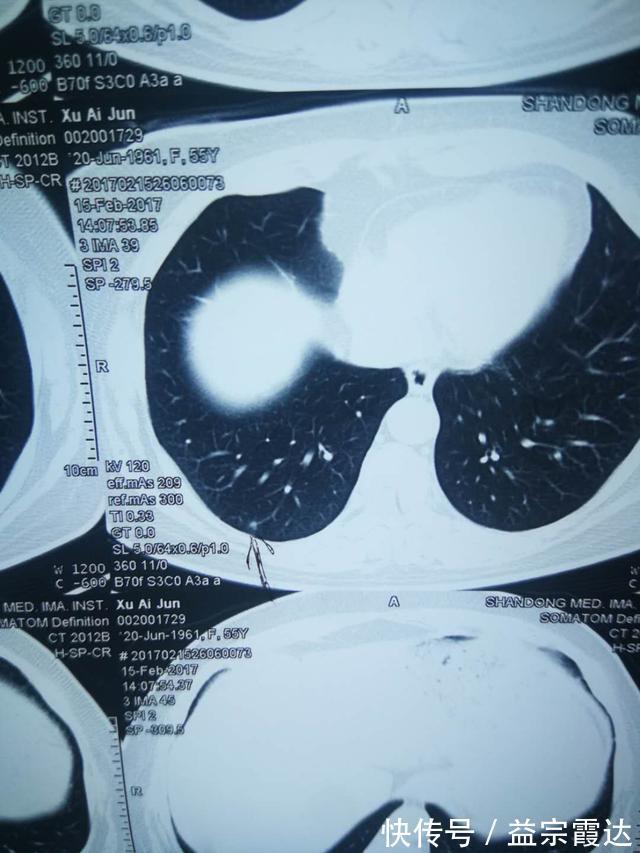

>真实案例许女士,61岁,乳腺癌术后肺结节,出现咳嗽,易急躁,胸闷,善太息,汗多,睡眠差多梦,易惊恐,舌暗红苔黄,许女士从山东卫视的《大医本草堂》节目中,看到李主任在肺结核方面颇有研究,于是找李主任看诊。

>许女士的CT报告北京中医药大学东方医院 肿瘤科主任 / 副教授 / 硕士生导师国家肿瘤微创联盟中西医结合肿瘤微创专委会候任主委BTV《养生堂》、山东卫视《大医本草堂》特约专家